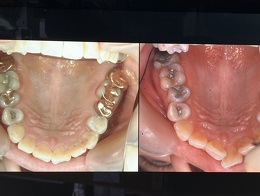

治療前後 彼女にはうつ病・不妊が治ることを伝えるため写真公開する許可を頂いています。

口呼吸による歯列の変形上顎

口呼吸による下顎歯列の変形

写真の看護師には全国で写真を見せてもよいと許可を取っています。食の誤りは種々な症状で現れますが彼女の予診票ではうつ病・不妊・便秘・冷え性・生理不順・肥満・虫歯・歯列不正とあります。根っこは一つです。根っこを直せば全てが解消します。